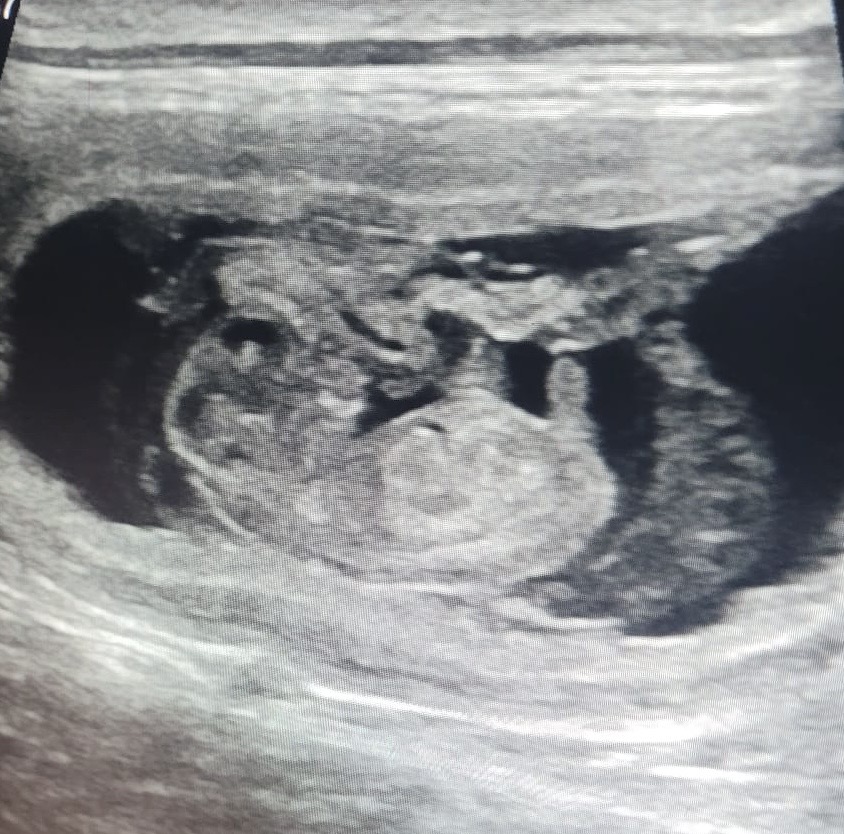

Bij kennel Sunny Dog Of Life worden pupjes verwacht uit Cato en Kyan 🎉 Cato; Just Add Water Be My Valentine is het zusje van onze Lizzy en dochter van Philou. Kyan; Best Kept Secret Of Beskyd Hill (Imp.CZ) is de zoon van Multi Ch. Diamante Blu Nella Mia Stanzan een reu die veel gewonnen heeft, en zich bewezen heeft op show en werkgebied. Er worden zwarte pupjes verwacht. Hartelijke felicitaties Christel en Desiree met jullie aanstaande nestje, wij kijken erg uit naar die lieve kleintjes 🥰